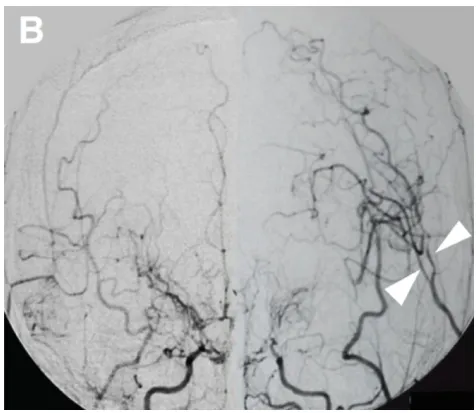

幸子需要早期手术血运重建,但甲状腺毒症被认为是手术的。开始强化甲状腺激素治疗,大约70天后达到激素缓解(图2A)。进行左侧STA-MCA搭桥术。由于术后不久观察到左MCA区域的高血流灌注现象(图3A),因此给予巴比妥酸盐昏迷治疗3天。术后未发生额外的缺血性和出血性并发症(图2B,C)。入院时神经功能缺损MRS评分为4分、重度残疾标准,术后3个月时恢复2分轻度残疾,无需协助下可以完成日常起居之事。

▼B,术后20天血管造影显示旁路通畅(箭头)。

对于伴有进展性GD的烟雾病,治疗的一步是通过使用抗甲状腺药物减少甲状腺激素的合成,一般使用甲巯咪唑和丙硫脲嘧啶。在某些情况下,放射性碘被用来控制甲状腺激素的合成。-肾上腺素能阻滞剂适用于控制甲状腺毒性症状,如高血压和心动过速。支持性治疗如静脉输液、输氧和冷却是维持血液循环所必需的。另一方面,需监测患者抗甲状腺药物的不良反应,如粒细胞缺乏症、肝损伤、胆汁性便、瘙痒、腹痛、恶心和血管炎。此外,由于碘诱发甲状腺功能亢进的风险已被报道,在甲状腺中毒的情况下,也应避免使用含碘造影剂进行脑血管造影。这就是为什么我们只对患者进行MRA,而不是在手术后一周进行常规血管造影。然而,在术后随访中,我们有时会进行常规血管造影以确认通畅。如图3B所示。